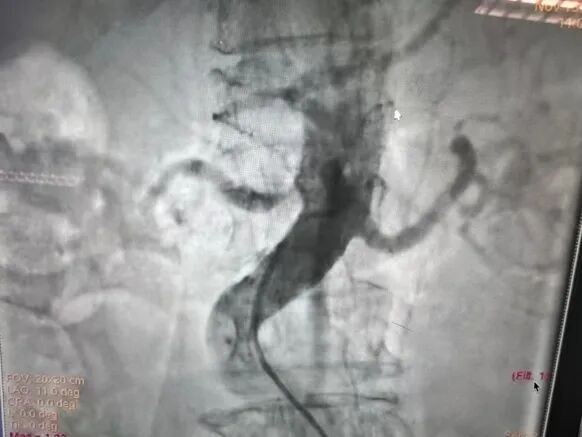

2.导管配合0.035导丝进入腹主动脉下端,造影示:腹主动脉走形迂曲,血流通畅,右肾动脉主干起始段重度狭窄>90%,远端及分支显影浅淡。

3.换鞘管后引入导丝及导管置于右肾动脉开口处,冒烟确定右肾动脉位置,换0.014in及0.018in导丝通过狭窄段后置于右肾动脉远端分支,经导丝引入3*40mmPTA快速交换球囊预扩狭窄段。

4.导丝支撑下交换引入CWB60605L-18震波球囊扩张右肾动脉狭窄段,完毕后复查造影示右肾动脉通畅,血管残余狭窄<20%,扩张效果满意,术毕。